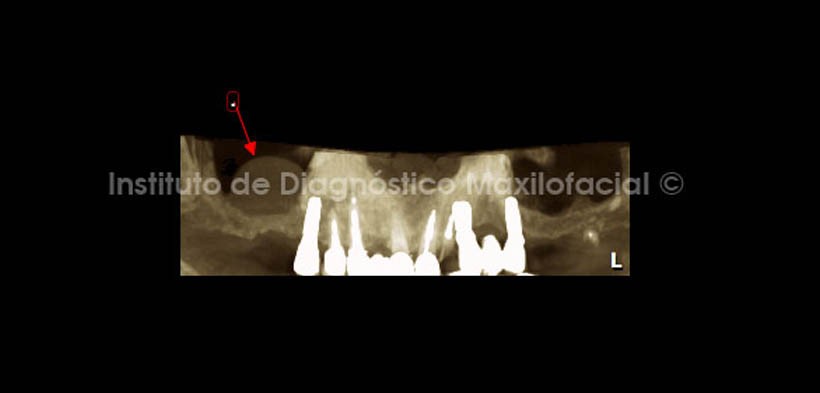

Las reformaciones panorámicas nos muestran imágenes semejantes a la de la radiografía (Fig. 2 y 3).